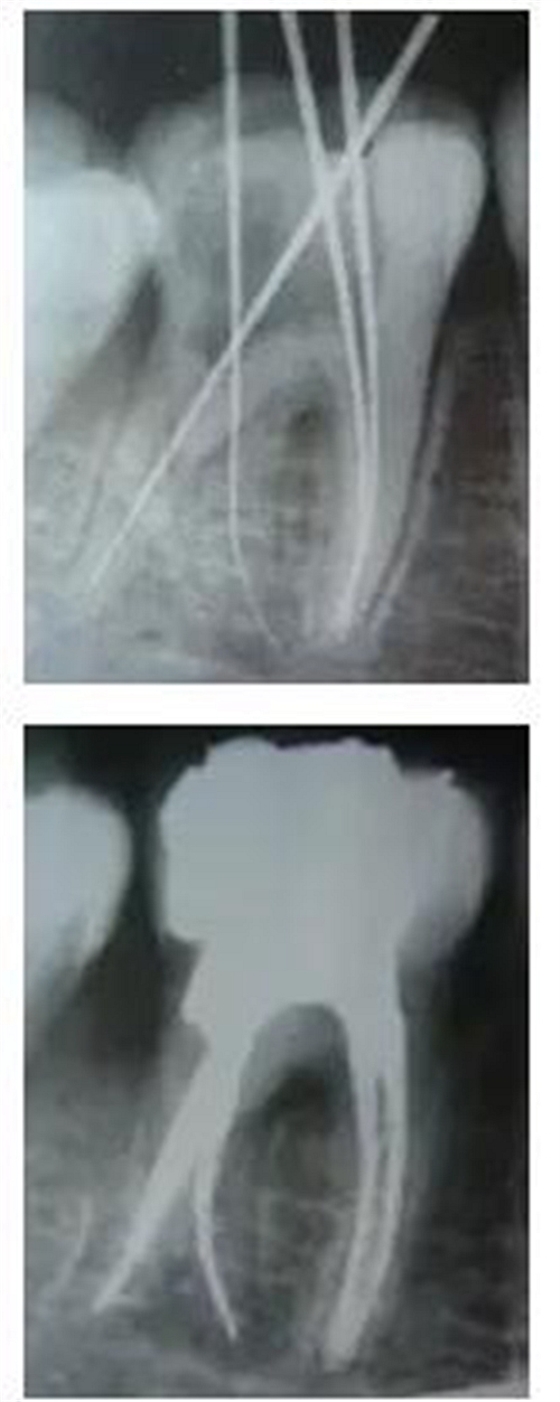

最后來玩一個(gè)根管治療質(zhì)量的評(píng)估——下圖是武大彭彬教授的一個(gè)病例,仔細(xì)觀察可以挑出一點(diǎn)問題,但問題事出有因!看看你的“眼力”如何——問題在那里?教授的專業(yè)水平是不用懷疑的,那么事出的原因可能是什么?

再次分享根管治療的點(diǎn)滴見解! 再次分享根管治療的點(diǎn)滴見解!

問題答案:這個(gè)病例的問題主要反應(yīng)在開髓的洞形修整,注意觀察該牙X-RAY的左側(cè)洞壁,如果常規(guī)情況制備成這樣是由于裂鉆破壞了洞壁和洞底所形成的臺(tái)階。如果評(píng)估根管治療的質(zhì)量那是要扣分的!但這個(gè)病例仔細(xì)觀察洞壁形態(tài)就可以看出:該病例屬于再治療的病例,因此還是屬于一個(gè)理想的病例。